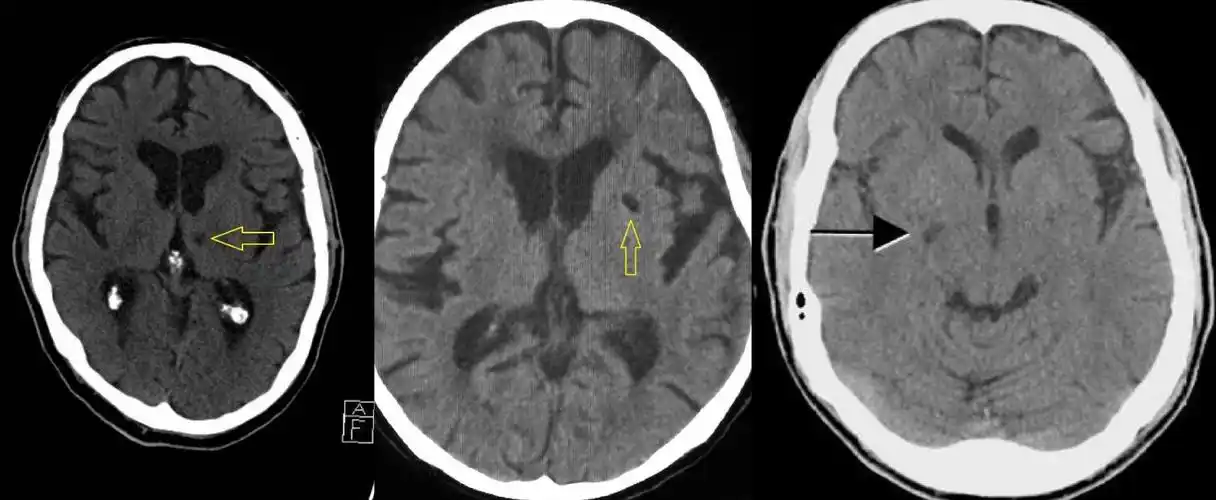

术前头颅ct可见右侧大脑中动脉血栓 aspects评分 10分

脑梗塞ct图